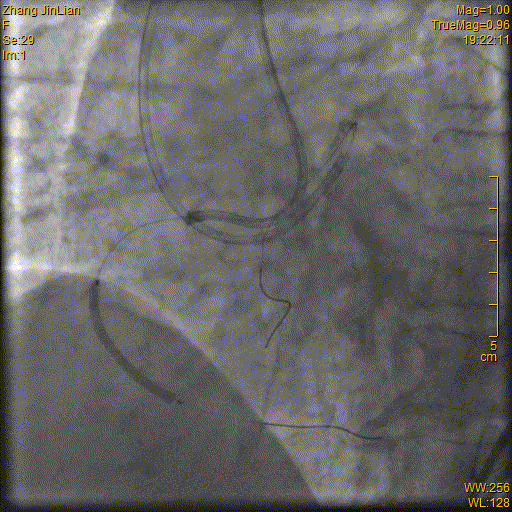

4. RCA PCI:Runthrough导丝保留在LAD行逆向PCI准备,Runthrough导丝引导Corsair150MC进入RCAm, 更换Fielder XTR导丝远端打弯(图11),导丝升级为PILTOT150耐心操作进入远端真腔(图12),Corsair150MC通过闭塞段(图13),更换工作导丝,2.0×15mm球囊扩张RCAm-d扩张后仍有明显狭窄(图14),2.5×29mm、2.75×23mmFirebird2DES串联植入RACp-d(图15-16),后三叉以远不显影,预计严重狭窄(图17),2.0×15mm球囊扩张后狭窄改善(图18),在Guidezilla延长导管支撑下20×23mm药物球囊扩张扩张后三叉60sec,最终效果满意(图19-20)。

图15

图16